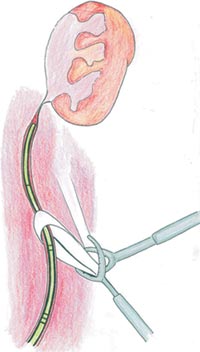

With the patient in lithotomic position, a cystoscopy is performed with the accomplishment of a retrograde ureteropyeloghaphy (Photo 1). Afterwards, a 7 F ureteral catheter is inserted with one tip placed bellow the ureteropelvic junction and the other outside the urethra connected to an 8 F Levine catheter. (Figure1).

Figure 1 - Diagrammatic representation of the exact position of the catheter over the UPJ and the other distal tip outside the urethra.

Figure 2 - Diagrammatic representation of the ureteral catheter increasing the ureter consistency.

Transperitoneal access was used; however, retroperitoneal access is also feasible. The intra-ureteral catheter facilitates its identification (Figure 2 and Photo 3). The ureter is traced cephalad toward the renal pelvis. NS (normal saline) 0,9% can also be injected through Levine catheter to distend even more the renal pelvis facilitating its identification (Figure 3 and 4). A 3.0 long straight needle could be passed percutaneously or not to lift the pelvis and therefore saving a trocar (Photo 4).